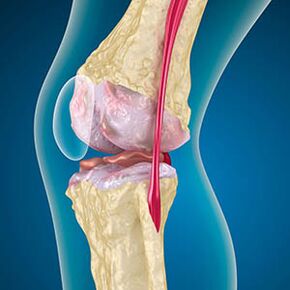

As the joints work, the cartilage at the edge of the bone is worn or completely absent.The damaged tissue is not the source of pain because it has no receptors.Inflammation of nearby structures can lead to characteristic symptoms.

The body continues to regenerate damaged tissue, but the cartilage grows unevenly.As a result, irregularities are formed that damage other elements of the joint.The properties of bone plants are explained by compensation for smoothing articular cartilage.Another version shows the growth of the "Spurs"Due to weakening of the muscle, it is related to attempts to stabilize the medial or lateral joints.

In the first stage of the joint, which was detected by chance, with a slight increase in bone spur occurrence.Growth occurs in the most unstable parts of the joints.Usually, patients rarely experience pain or discomfort during exercise.

The second stage of the joint is considered easy.X-rays showed obvious bone spurs, but the cartilage was not affected.The amount of synovial fluid has decreased, but there are symptoms of pain after walking and running for a long time, stiffness during bending, and pain in knee positions.